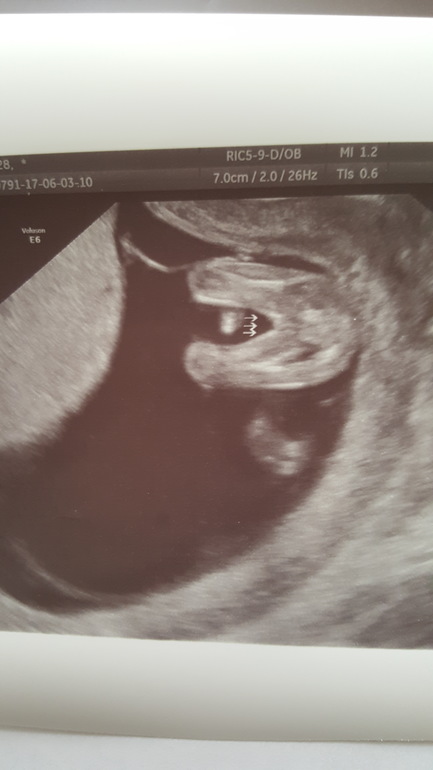

Скрининг и пол в 11,6 недель по М

В общем девочки сходили мы на 1 скрининг - по узи..ура..все хорошо. Единственное предлежание у нас..

КТР 65,3

ТВП 1

БПР 16,9

нос 2

Ну еще конечно все остальное тоже измерили и все крсточки посмотрели.

Теперь кровь дождаться и не сойти с ума. Пришли по М 11,6 по развитию на 12,6😉

И самое интересное нам сегодня предположили пол ..

Даже не верится - доченька! 👸

Лицо упорно не хотели показывать. Нос измерили со второго раза...когда меня уже отправили ходить😂...я даже прыгала, пыталась ее разбудить.

А во время узи и крутилась и кашляла..ноль реакции дрыхнет и все))) к нам спиной😴

Меня чет все и мама моя со своей интуицией настроили на мальчика, я уж даже вещи смотрела мальчишечьи. Понимаю это не 100%...но наш врач экспертного узи сказала скорее всего. Причем сразу как ее увидела она еще тогда немного крутанулась прежде чем улечься спать, потом перепроверели попу с писей разглядели) врачу доверяю..но конечно недель в 14-16 перепроверим